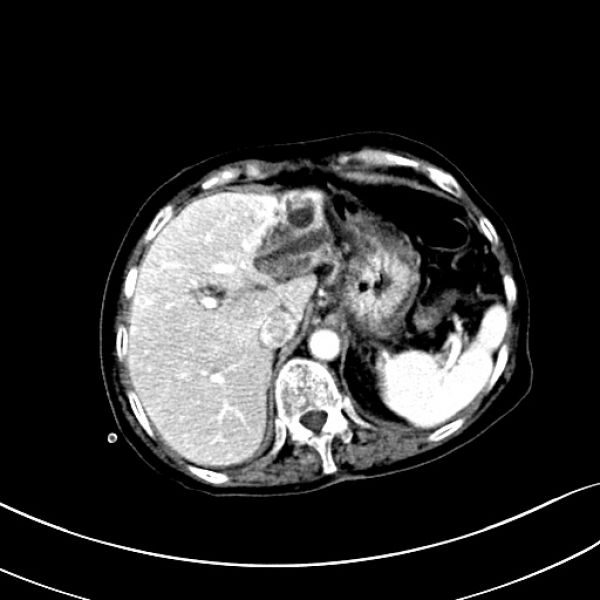

随着进一步检查的完善,患者诊断逐步明确:1.肝胆管结石(区域型), 2.胆囊结石伴胆囊炎, 3.胆总管结石伴梗阻性胆管炎。

术前影像学资料